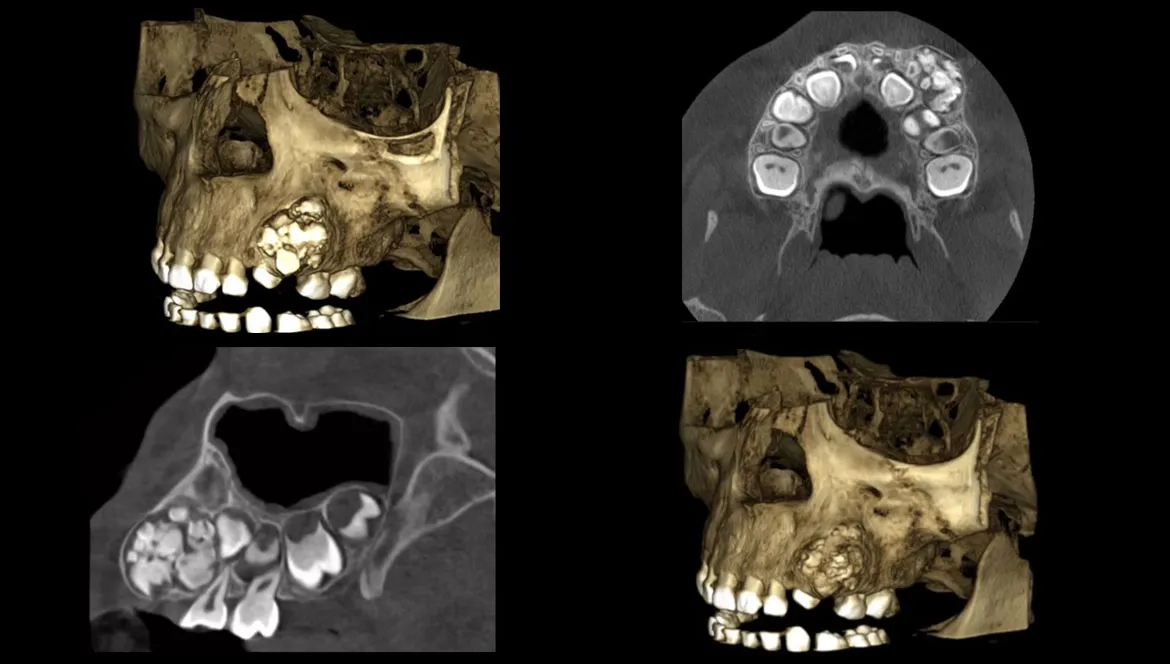

TOMOGRAFÍAS

Contamos con las siguientes tomografías:

• Tomografía de Maxilar Superior.

• Tomografía de Maxilar Inferior.

• Tomografía de ambos Maxilares.

• Tomografía de ATM: Boca Cerrada / Boca Abierta.

• Tomografía Maxilofacial.

• Tomografía de Pieza Dentaria.

Radiopacas intraósea

Presencia de 3 imágenes radiopacas intraósea de densidad dentaria compatible con odontomas compuestos proyectados.

• 2 en zona de pieza 11

• 1 en zona de pieza 43

Odontoma Compuesto

Imagen hiperdensa localizada en el maxilar superior izquierdo, ocasionando el desplazamiento de la tabla ósea bucal y desplazamiento palatino de la pieza 2.4.